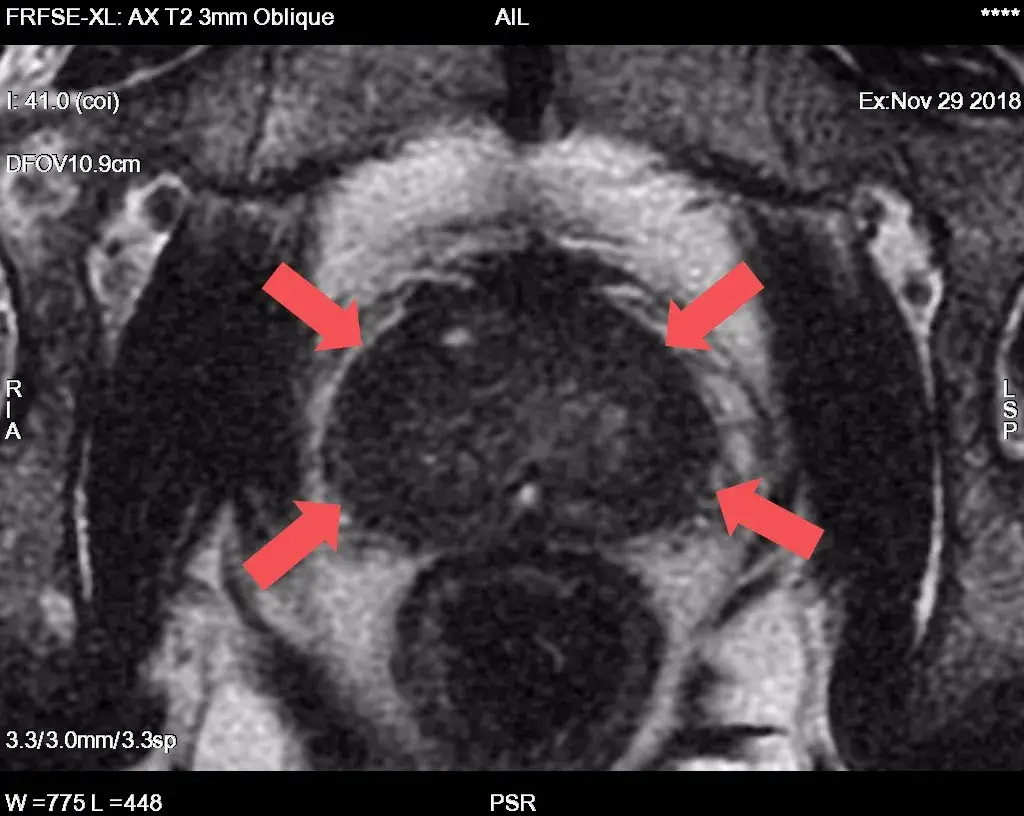

Czym dokładnie jest wieloparametryczny rezonans prostaty (mpMRI)? To nie jest standardowy rezonans miednicy mniejszej, który mógł być wykonywany wcześniej. mpMRI wykorzystuje specjalistyczne sekwencje obrazowania, które pozwalają na ocenę różnych parametrów tkanki gruczołu krokowego. Aby badanie było wiarygodne, kluczowe jest wykonanie go na aparacie o wysokim polu magnetycznym minimum 1.5 Tesli, a najlepiej 3 Tesle. Tylko takie urządzenia zapewniają odpowiednią rozdzielczość i jakość obrazu niezbędną do dokładnej oceny.

mpMRI wykorzystuje zaawansowane techniki obrazowania, w tym sekwencje T2-zależne, dyfuzyjne (DWI) oraz dynamiczne z podaniem środka kontrastowego. Każda z tych sekwencji dostarcza informacji o innych właściwościach tkanki. Na przykład, sekwencje dyfuzyjne oceniają ruchomość cząsteczek wody w tkankach, co jest zaburzone w komórkach nowotworowych. Analiza wszystkich tych parametrów łącznie pozwala radiologowi na identyfikację obszarów, które odbiegają od normy i mogą być potencjalnie złośliwe.